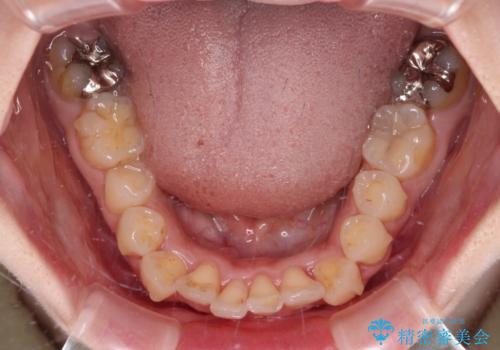

左右ともに、上顎第二大臼歯が欠損しており、下顎の第二大臼歯が十分に咬み合う歯がない状態のため、放置しておくと下顎の奥歯が挺出してくる可能性があります。

安定した咬み合わせを維持するためにも、将来的に上左右にインプラント補綴が必要となります。